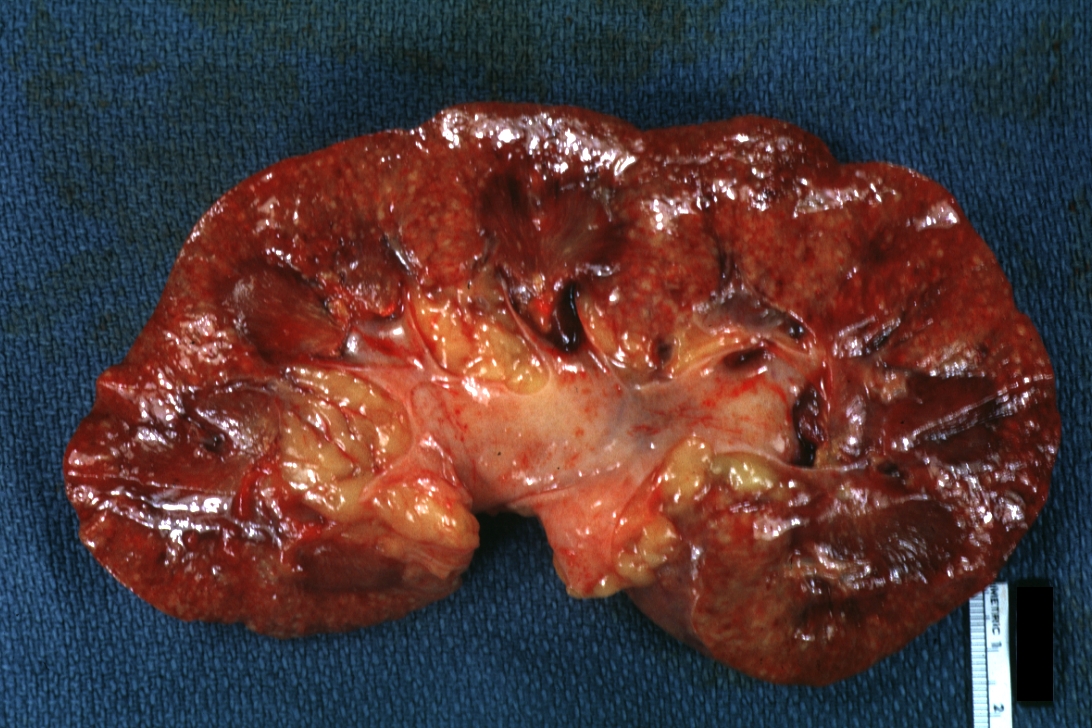

GROSS: Urinary: Kidney: Acute Pyelonephritis: Gross natural color hemisection of kidney with multiple small abscesses and pyelitis Candida